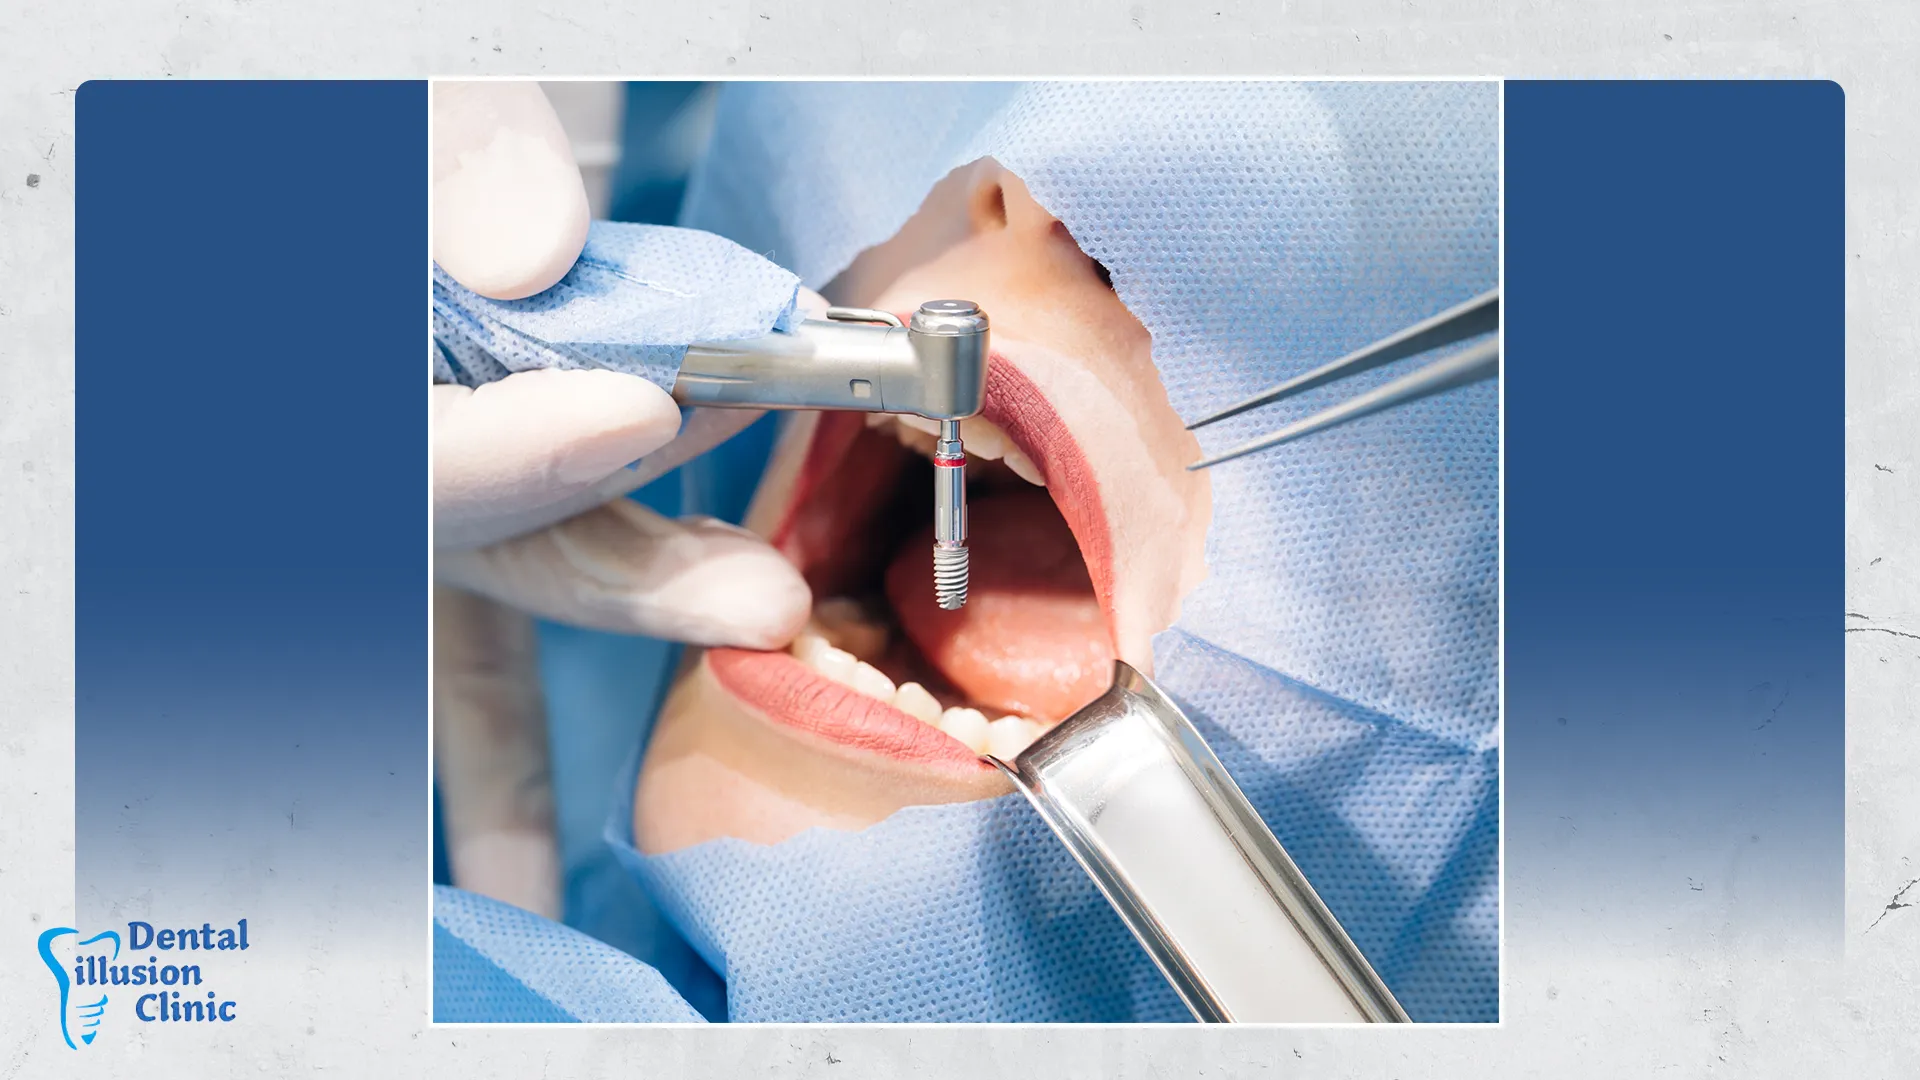

يُعد خلع الأسنان الجراحي إجراءً متقدمًا نلجأ إليه كحل علاجي أخير في الحالات المُعقدة التي لا يمكن علاجها بالوسائل التقليدية. وفي عيادة إلوجن لطب الأسنان نقوم بهذا الأجراء بأعلى درجات الدقة باستخدام تقنيات حديثة وتخدير متطور لضمان تقليل الألم وتسريع التعافي والحفاظ على صحة الفم والأنسجة المحيطة.

خلع الأسنان الجراحي هو إجراء طبي متقدم يعتمد على تدخل جراحي دقيق لفتح اللثة وإزالة السن التالف وجذوره بأمان بعد تقييم شامل بالأشعة والتشخيص الدقيق، ويُجرى في الحالات المعقدة التي لا يمكن علاجها أو خلعها بالطريقة العادية خاصةً في ضروس العقل المعقدة، مثل الأسنان المدفونة داخل عظم الفك، أو المكسورة أسفل مستوى اللثة، أو المصحوبة بالتهابات شديدة وخراجات تُمثل تهديدًا للأسنان المجاورة.

يُعد خلع الأسنان الجراحي حلًا طبيًا ضروريًا في الحالات المعقدة التي لا يصلح معها الخلع العادي، ويتميز بعدة فوائد صحية وعلاجية، من أبرزها: